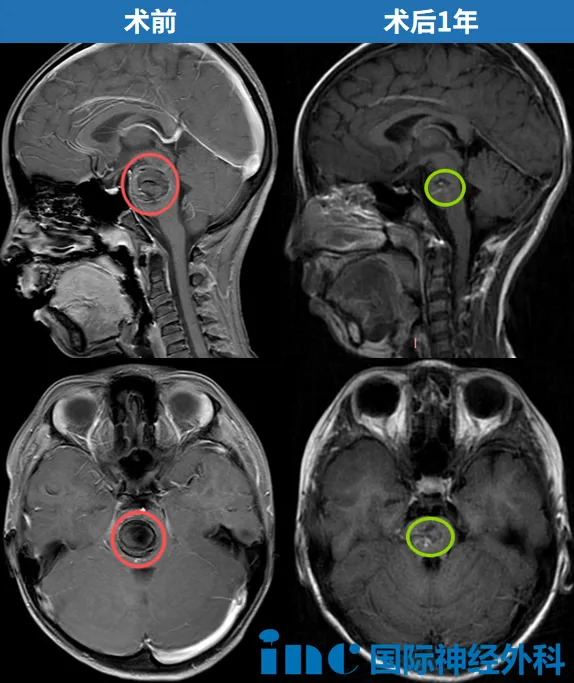

回到这次温馨的重逢现场,巴教授仔细查看了萌萌最新的核磁共振片子,用标准的中文说:"太好了!"